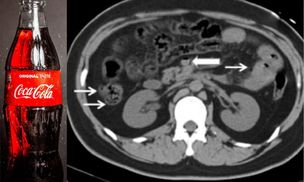

Wypił 1,5 litra coli. Nie żyje. Podali przyczynę zgonu 22-latka